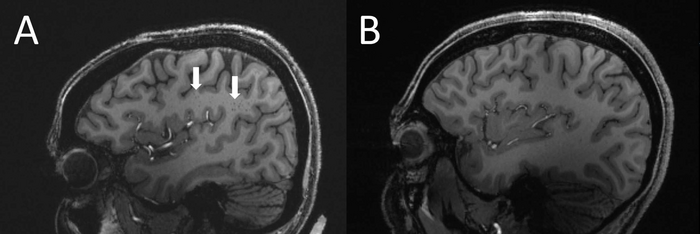

(A) Enlarged centrum semiovale (CSO) perivascular spaces (PVS) (arrows) on sagittal T1-weighted MRI in a case with chronic migraine. (B) Migraine-free control without enlarged CSO PVS.